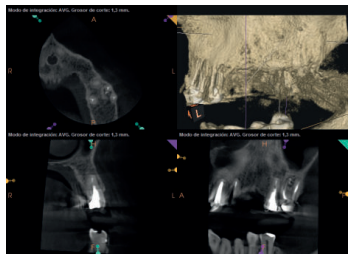

Para confirmar el origen endodóntico y el tamaño de las lesiones se realizaron exploraciones tomográficas con espesor de corte de 75 micras mediante CBCT CS8100 (Carestream Dental® ) en las que se evidenciaron lesiones periapicales radiolúcidas a nivel de 12, 11, 21 (con afectación bicortical), 25 y raíces vestibulares de 26 (Figuras 4 a 8).